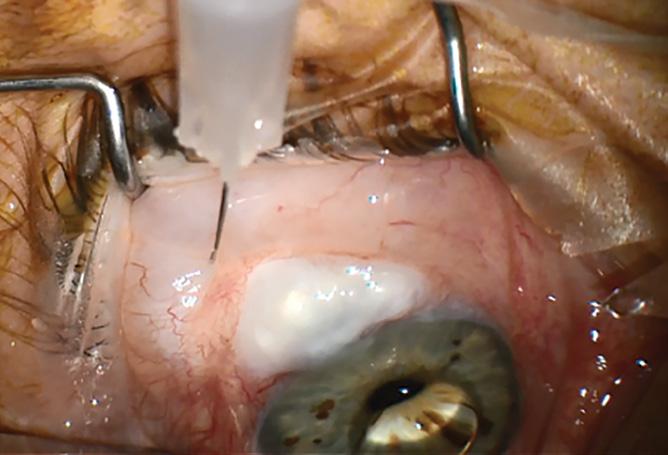

Post-paediatric cataract surgery Glaucoma: A: 3.5 years old child with cataract surgery done in infancy. Glaucoma with enlarged corneal diameter and a dislocated IOL are seen. One previous Ahmed glaucoma valve (AGV) in supero-temporal quadrant has failed to control IOP adequately; B: A second AGV plate is sutured in the infero-temporal quadrant. A closed chamber vertical translocation of haptics to glued IOL is then done sitting temporally, taking advantage of smaller vertical diameter of cornea; C: Adequate length of the externalised haptics of the IOL is seen; D: Haptics are tucked in. A well-centred IOL is seen. The AGV tube tip is positioned posterior to the iris in front of the IOL. Adequate vitrectomy is performed during IOL translocation as well as after inserting the tube tip